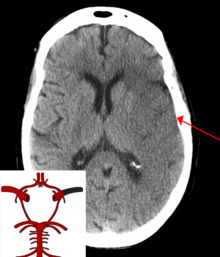

CT scan of an intraparenchymal bleed (bottom arrow) with surrounding edema (top arrow)

There are two main types of hemorrhagic stroke:[28][29]

• Intracerebral hemorrhage, which is basically bleeding within the brain itself (when an artery in the brain bursts, flooding the surrounding tissue with blood), due to either intraparenchymal hemorrhage (bleeding within the brain tissue) or intraventricular hemorrhage (bleeding within the brain's ventricular system).

• Subarachnoid hemorrhage, which is basically bleeding that occurs outside of the brain tissue but still within the skull, and precisely between the arachnoid mater and pia mater (the delicate innermost layer of the three layers of the meninges that surround the brain).